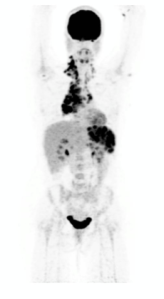

PET Scan Number Two

screen shot 2019-01-21 at 11.46.56 am

January 21, 2019